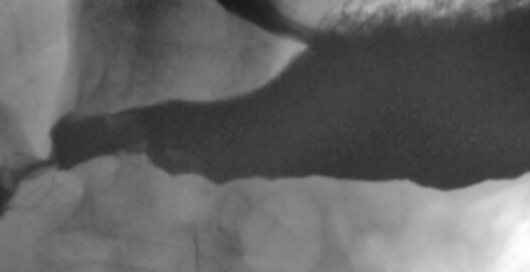

Пищевод.

дивертикулы пищевода

Изображение  Изображение

Естественно есть признаки дивертикулита- в 1ю очередь слабо выражено, но 3-х слойность за счет наличия слизи.

"выпячивание" стенки пищевода, указанное над диафрагмой вероятнее всего ГПОД, склдки желудочного типа.